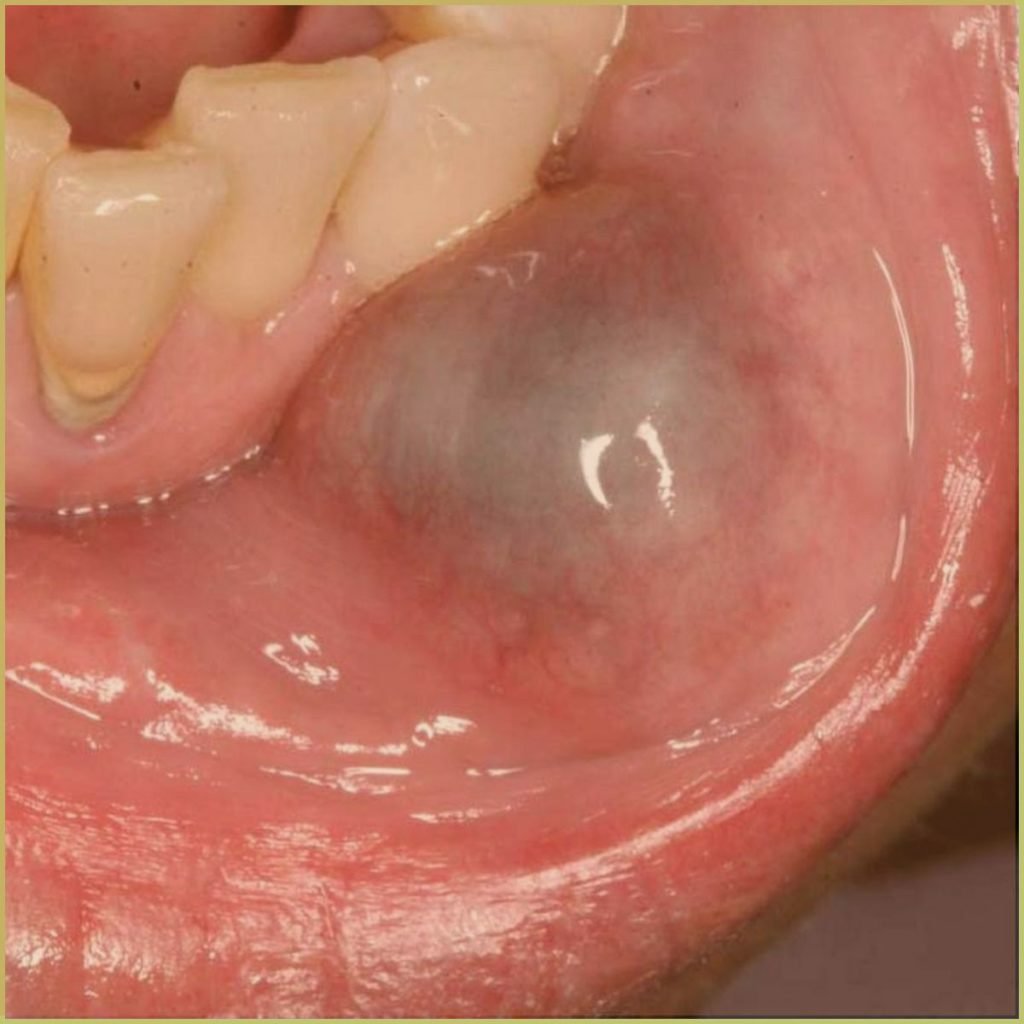

MUCOCELE

A mucocele is a common benign mucus-containing cystic lesion that is caused by mucus accumulation and swelling of a minor salivary gland. The two subclassifications are 1) mucus extravasation cyst, and 2) mucus retention cyst. Extravasation mucoceles result from a damaged salivary gland duct and subsequent spillage into the surrounding soft tissues. Retention mucoceles result from a blockage of the salivary gland ducts. The common clinical presentation includes:

- Painless bluish swelling when mucin is near the surface.

- Commonly seen on the lower lip, but can affect buccal mucosa and the anterior ventral surface of the tongue.

- Often waxes and wanes in size.